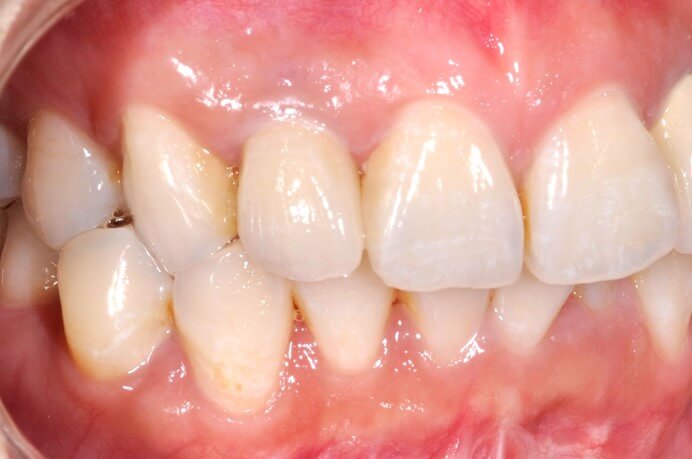

美觀區植牙通常是用於前牙的區域,對於美學較有要求的部位。相較於一般植牙,美觀區植牙更須要注重牙齒美學的考量。另外前牙區的骨壁較薄,缺牙後會有較多的骨質流失,頰側的骨頭容易凹陷。也因此前牙植牙是較具挑戰性的,植牙前各方面的謹慎評估會比一般後牙區植牙來得複雜許多

牙齦塑形來模仿自然牙齒的型態

模仿自然牙齒的全瓷假牙安裝

安裝後側面

正面